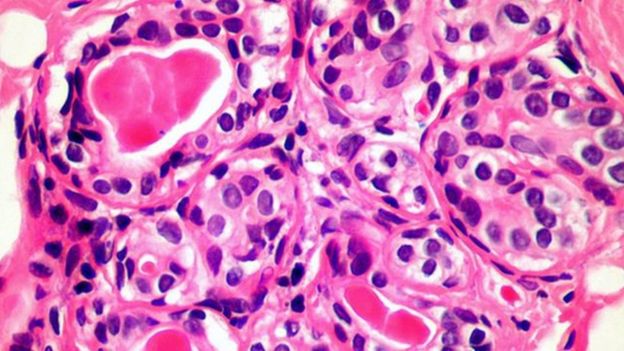

مصدر الصورةSCIENCE PHOTO LIBRARYويتفاعل مُستقبل الخلية التائية مع جزيء يُسمى MR1، وهو موجود على سطح كل خلية في الجسم البشري.